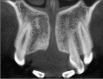

Cone beam computed tomography (CBCT) scanners for the oral and maxillofacial region were pioneered in the late 1990s independently by Arai et al. in Japan and Mozzo et al. CBCT has a lower dose of radiation, minimal metal artifacts, reduced costs, easier accessibility, and easier handling than multislice computed tomography (MSCT); however, the latter is still considered a better choice for the analysis of bone density using a Hounsfield unit (HU) scale. Oral implants require localized area of oral and maxillofacial area for radiation exposure; so, CBCT is an ideal choice. CBCT scans help in the planning of oral implants; they enable measurement of the distance between the alveolar crest and mandibular canal to avoid impingement of inferior alveolar nerve, avoid perforation of the mandibular posterior lingual undercut, and assess the density and quality of bone, and help in planning of the oral implant in the maxilla with special attention to the nasopalatine canal and maxillary sinus. Hence, CBCT reduces the overall exposure to radiation.